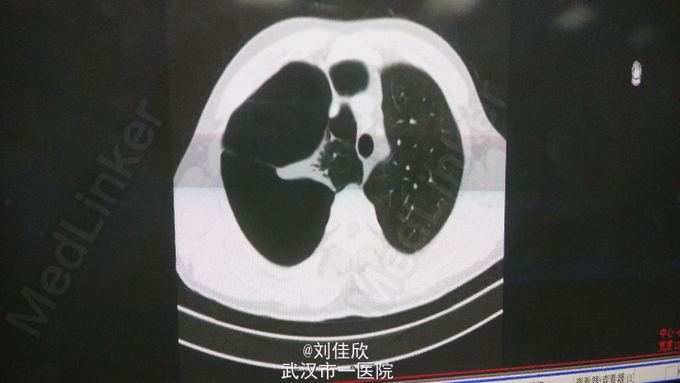

查体:右肺呼吸音低,余查体(-)。 辅助检查:当地医院胸片示:右肺肺大疱,右肺压缩约90%。6-10:肺、纵隔平扫:1.右肺大量气胸,肺组织压缩至纵隔旁呈三角形,肺组织压缩90%左右,右肺门影增大,建议复张后随访复查排除病变。2.右侧胸膜呈结节状或结片状增厚并部分胸膜粘连;3.右侧胸膜腔少量积液。4.左肺上叶及下叶胸膜下多发微小斑点状结节影,直径约1-2mm。(见下图)